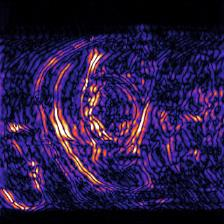

Recently, deep neural networks have greatly advanced undersampled Magnetic Resonance Image (MRI) reconstruction, wherein most studies follow the one-anatomy-one-network fashion, i.e., each expert network is trained and evaluated for a specific anatomy. Apart from inefficiency in training multiple independent models, such convention ignores the shared de-aliasing knowledge across various anatomies which can benefit each other. To explore the shared knowledge, one naive way is to combine all the data from various anatomies to train an all-round network. Unfortunately, despite the existence of the shared de-aliasing knowledge, we reveal that the exclusive knowledge across different anatomies can deteriorate specific reconstruction targets, yielding overall performance degradation. Observing this, in this study, we present a novel deep MRI reconstruction framework with both anatomy-shared and anatomy-specific parameterized learners, aiming to "seek common ground while reserving differences" across different anatomies.Particularly, the primary anatomy-shared learners are exposed to different anatomies to model flourishing shared knowledge, while the efficient anatomy-specific learners are trained with their target anatomy for exclusive knowledge. Four different implementations of anatomy-specific learners are presented and explored on the top of our framework in two MRI reconstruction networks. Comprehensive experiments on brain, knee and cardiac MRI datasets demonstrate that three of these learners are able to enhance reconstruction performance via multiple anatomy collaborative learning.